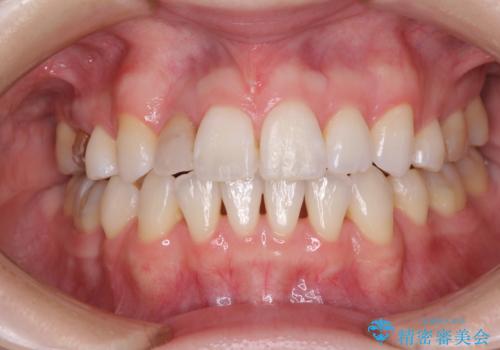

変色した前歯 オーダーメイドタイプのオールセラミッククラウン

他院で矯正治療をされていたそうですが、矯正治療前から変色は気になっており、歯並びが整ってからは、より気になるようになっていたそうです。

自然に仕上がり、患者様には大変満足していただきました。